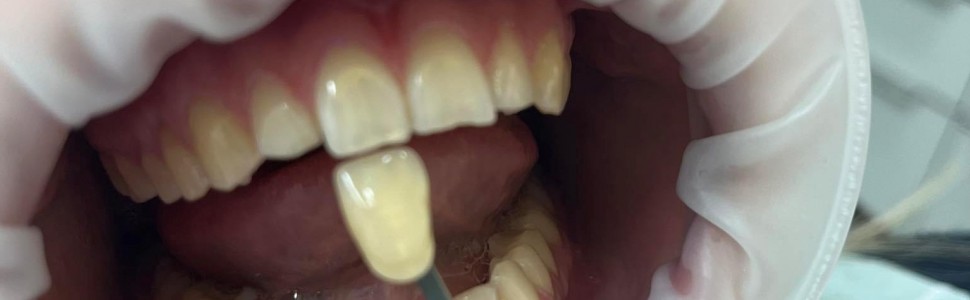

W artykule zaprezentowano opis przypadku wybielania nakładkowego (preparat Opalescence PF 16%, producent: Ultradent Products) u 22-letniej ogólnie zdrowej pacjentki. Wybielanie nakładkowe to jedna z najpopularniejszych metod wybieranych przez pacjentów, łącząca poprawę koloru zębów w gabinecie stomatologicznym z samodzielną pracą pacjenta w domu z wykorzystaniem nakładki termoformowalnej, na którą według instruktażu pacjent samodzielnie nakłada preparat wybielający w formie żelu o dobranym stężeniu. Wizyty pacjenta można podzielić na dwa etapy. Podczas pierwszego przeprowadzane jest badanie i kwalifikacja do zabiegu wybielania. Wykonuje się profesjonalne oczyszczanie zębów, a następnie pobiera wycisk z zastosowaniem masy alginatowej na łyżkach standardowych i oddaje się do pracowni technicznej w celu wykonania modeli gipsowych i indywidualnych nakładek termoformowalnych. Podczas drugiego etapu pacjent otrzymuje gotowe nakładki oraz strzykawki z dopasowanym rodzajem oraz stężeniem substancji aktywnej żelu wybielającego. Pacjentowi udzielany jest instruktaż użytkowania wraz z zaleceniami. Cały proces trwa od 2 do 4 tygodni w zależności od mocy preparatu, rodzaju przebarwień oraz czasu stosowania. Pacjenta obowiązuje biała dieta w trakcie wybielania, jak i po jego zakończeniu przez zalecany okres 2 tygodni oraz bezwzględny zakaz palenia tytoniu.

In this article we present a case report of overlay bleaching (Opalescence PF 16%, manufacturer: Ultradent Products) in a 22-year-old generally healthy patient. Overlay bleaching is one of the most popular methods chosen by patients, combining the improvement of tooth color in the dental office with the patient's independent work at home using a thermoformable tray, onto which, according to instructions, the patient independently applies a bleaching preparation in the form of a gel with a selected concentration. Patient visits can be divided into two stages. During the first, an examination and qualification for the bleaching procedure is carried out. A professional cleaning of the teeth is performed, and then an impression is taken using alginate compound on standard impression trays and returned to the technical laboratory for making gypseous models and individual thermoformable trays. During the second stage, the patient is given the finished trays and syringes with the matching type and concentration of the active ingredient of the bleaching gel. The patient is given instructions for use along with recommendations. The entire process takes from 2 to 4 weeks, depending on the strength of the preparation, the type of discoloration and the duration of application. The patient is obliged to follow a white diet during the whitening process, as well as after its completion for a recommended period of 2 weeks, and an absolute prohibition on smoking.